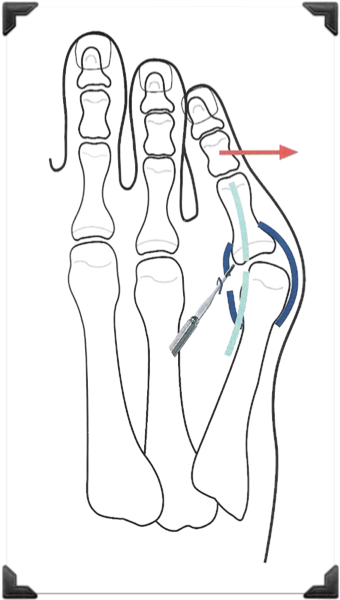

Dedo Supraducto - Metatarsalgia

Pre y Post op

Dr. Luis Villanueva

Dr Meyerson (USA)